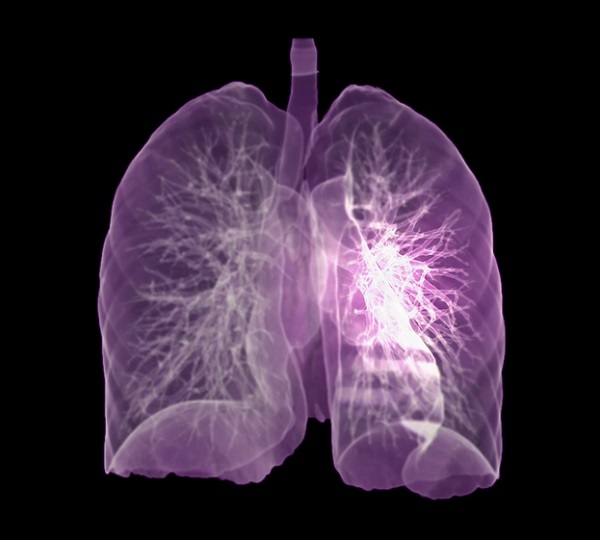

객혈

폐암의 또 다른 초기 증상은 객혈입니다. 객혈은 혈액을 토하거나 혼합혈 가래가 계속 나오는 것을 말합니다. 구토가 지속되거나 혈액과 섞이면 의사의 진찰을 받는 것이 좋습니다.

두통, 현기증

뇌는 또한 폐암이 전이되는 장소 중 하나입니다. 폐암의 증상으로는 두통, 구토, 드물게 발작이 있습니다. 다른 신체 증상으로는 악액질, 구토, 가스, 식욕 부진 및 체중 감소가 있습니다. 그 중 악액질은 이른바 둠스데이로 혈우병, 결핵, 암 등 악성질환이 말기에 접어들면 나타나는 고도로 쇠약해진 상태를 말한다. 살이 빠지면 무기력해지고 발, 눈꺼풀 등 다양한 부위에 부종이 생길 수 있으며 심한 빈혈은 피부가 뿌옇고 노랗게 변할 수 있다.

가슴 통증

폐암의 초기증상 중에 흉통이 있습니다. 폐암 환자의 약 1/3이 흉통을 호소합니다. 흉통의 원인은 폐 가장자리에 종양이 형성되어 암세포를 생성하고 흉벽과 흉막에 침착되어 통증을 유발하는 것입니다.

흉통의 원인은 여러 가지가 있을 수 있지만, 오늘날 우리가 다루고 있는 폐암으로 인한 흉통은 경미한 통증보다는 지속적인 따끔거림과 둔한 통증을 동반한다는 점에 유의하시기 바랍니다. 또한 암은 흉막이나 흉벽 대신 갈비뼈로 퍼져 통증을 유발할 수 있습니다. 종양은 주변 조직 세포를 자극할 수 있으므로 계속해서 통증을 유발하는 경우 의사의 진찰을 받는 것이 좋습니다.